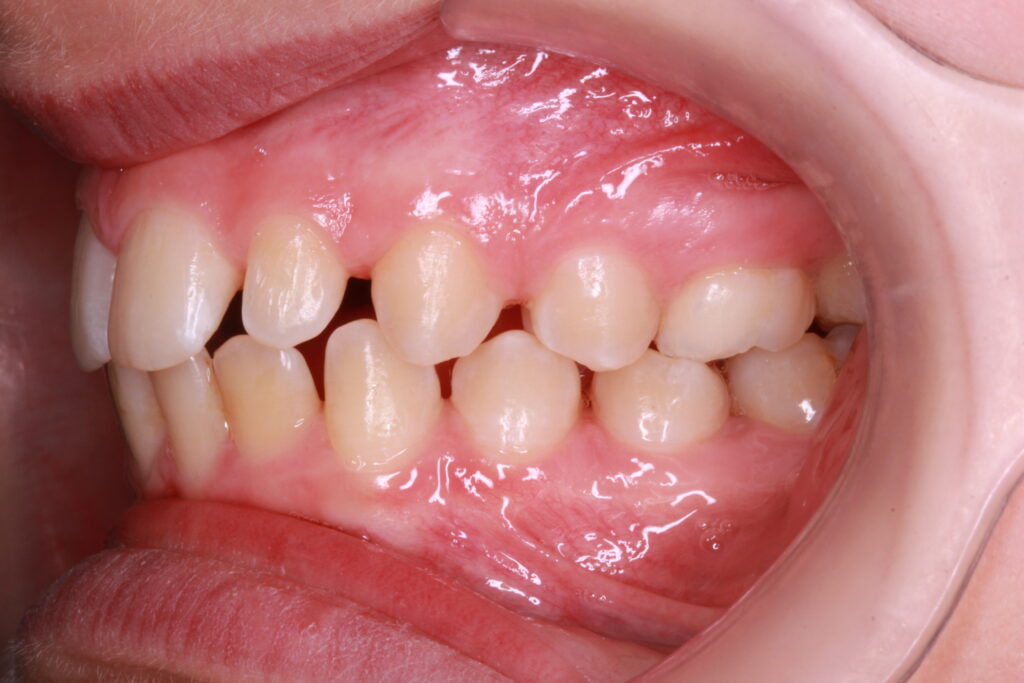

✔ Class II, Class III, aszimmetria és keresztharapás elméleti megközelítése

Az ALF készülék nem az agresszív erőhatásokra, hanem a funkcionális erők finom, biológiailag kíméletes irányítására épít. A klinikai tapasztalatok szerint ez tökéletes elég és mind a fogív fejlesztésében, keresztharapások megszűntetésében, helyteremtésben mind a nyelvtér növelésében jól működik.

A leggyakoribb a vegyes fogazat időszakában (6–11 év), de alkalmazható teljes tejfogazatban is nagyon korai kezelések esetében, akár 3-4 éves kortól is.